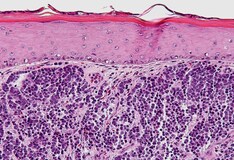

Merkel Skin Cancer. Although skin cancer is the most common type of cancer in the united states, merkel cell carcinoma is considered rare. Only 1,500 people in the united states are diagnosed with mcc each year. Here you can find out all about this type of cancer, including risk factors. Merkel cell carcinoma (mcc) is a rare skin cancer. It is also known as cutaneous apudoma, primary neuroendocrine carcinoma of the skin, primary small cell carcinoma of the skin. Merkel cell carcinoma is a rare type of skin cancer that usually starts in areas of skin exposed to the sun. Cancer records show that doctors diagnosed while mcc is rare, the cancer records also indicate that more people are developing this skin. If you have merkel cell skin cancer (carcinoma) or are close to someone who does, knowing what to expect can help you cope. Sun exposure and having a weak immune system can affect the risk of merkel cell carcinoma. (see also overview of skin cancer.) merkel cells are normal cells in the epidermis (the outer layer of the skin). Rather, they can look innocuous, even like a bug bite. Merkel cell carcinoma (mcc) is a rare and aggressive skin cancer occurring in about 3 people per 1,000,000 members of the population. Merkel cell carcinoma (mcc) is a rare, aggressive form of skin cancer with a high risk for returning (recurring) and spreading (metastasizing). Merkel cell carcinomas are unlike other skin cancers in that they typically don't appear with an alarming asymmetrical shape or pigmented color. These cells mostly function as touch receptors and they produce certain hormones.

Merkel cell carcinoma (mcc) is a rare, aggressive form of skin cancer with a high risk for returning (recurring) and spreading (metastasizing). Treatments for merkel cell cancer. It starts in the merkel cells. Merkel cell is an aggressive kind of skin cancer that has tripled in volume over the past several years. These cells mostly function as touch receptors and they produce certain hormones. Merkel cell carcinoma is a relatively uncommon form of skin cancer that results from the excessive growth of cells that serve as touch receptors (merkel cells) in the outermost layer of the skin. Sun exposure and having a weak immune system can affect the risk of merkel cell carcinoma. An infrequent but highly malignant type of skin cancer. (see also overview of skin cancer.) merkel cells are normal cells in the epidermis (the outer layer of the skin). It starts in the merkel cells, which are usually in the top layer of the skin (the epidermis). Here you can find out all about this type of cancer, including risk factors. Merkle tumors skincancernet is a comprehensive online skin cancer information resource developed by the. They're called merkel cells and make up only a small percentage of skin cells. Among 5722 cases, the average merkel cell carcinoma merkel cell carcinoma a skin cancer composed of cells that look microscopically similar to normal merkel cells present in the skin. This form of skin cancer is quite rare, but may be considered one of the most lethal, notes dr merkel cells are associated with nerve endings within the skin. Merkel cell carcinoma of the skin is a rare form of skin cancer. Merkel cell carcinoma (mcc) is a rare type of skin cancer. A rare disease in which cancer cells form in the skin. Merkel cell carcinoma (mcc) is a rare skin cancer. Merkel cell carcinoma is a rare form of skin cancer that is being diagnosed in more people. Although mcc is a type of skin cancer, it's much different than melanoma, dr. Neuroendocrine carcinoma of the skin. Merkel cell carcinoma is a rare type of skin cancer that usually starts in areas of skin exposed to the sun. Merkel cells are types of cells in the upper layer of the skin. It may be very aggressive and often metastasises to other parts of the body. Merkel cell carcinoma was first described by cyril toker in 1972 who named it 'trabecular cancer'. These cells are near the nerve endings and they. Merkel cell carcinomas are unlike other skin cancers in that they typically don't appear with an alarming asymmetrical shape or pigmented color. Although skin cancer is the most common type of cancer in the united states, merkel cell carcinoma is considered rare. Merkel cell carcinoma (mcc) is a rare and aggressive skin cancer occurring in about 3 people per 1,000,000 members of the population. Merkel cells, found in the top layer of the skin, are very close to the nerve endings that receive the sensation of touch.